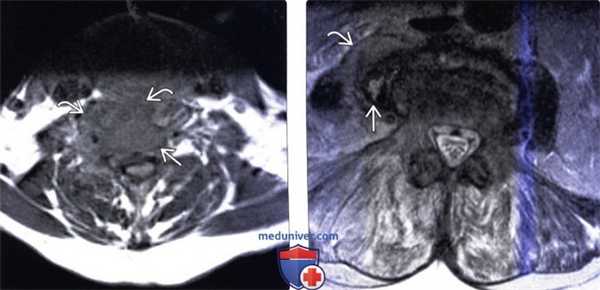

(Слева) Аксиальный срез, Т1-ВИ: аморфное низкоинтенсивное образование в области тела шейного позвонка и вентральной поверхности длинных мышц шеи. Паравертебральная флегмона стала следствием спондилодисцита.

(Справа) Аксиальный срез, Т2-ВИ: гетерогенное жидкостное образование в толще правой поясничной мышцы. Оно окружено толстой неправильной формы гипоинтенсивной стенкой, центральная часть отличается гиперинтенсивностью сигнала. Правая поясничная мышца с признаками диффузного усиления сигнала вследствие отека.

(Слева) Аксиальный срез, Т1-ВИ FS с КУ: ярко контрастирующееся гетерогенное паравертебральное жидкостное образование, окружающее переднюю и боковые поверхности тела поясничного позвонка. Накапливающие контраст ткани располагаются в непосредственной близости к аорте.

(Справа) Фронтальный КТ-срез: справа определяется паравертебральный абсцесс, сформировавшийся на фоне спондилодисцита. В полости абсцесса виден катетер. Гиперденсное внутреннее содержимое абсцесса может представлять собой продукты распада крови и гной.